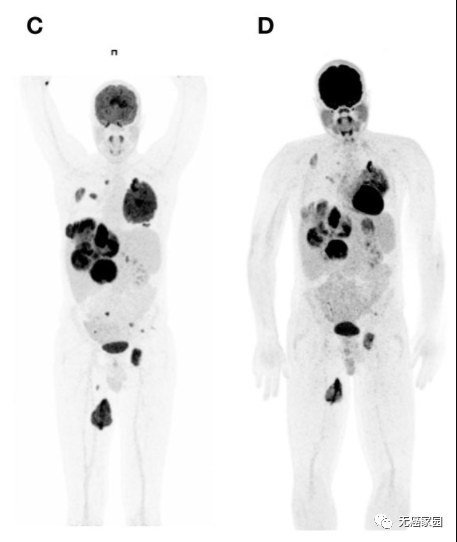

这是一名患有晚期、预处理的NTRK重排梭形细胞肿瘤和肝、肺和骨转移的26岁男性接受拉罗替尼连续28天的治疗,剂量为100 mg,每天2次。治疗7天后进行的18 FDG-PET/CT 扫描显示内脏和骨病变中的肿瘤缩小。随后的评估证实了疾病部位的肿瘤持续消退。患者情况良好,并继续治疗。

左图为治疗前 PET/CT 扫描,图中显示转移灶几乎占据了整个肝脏、左肋骨和左股骨;

右图为开始采用拉罗替尼治疗7天后,PET/CT扫描显示早期肿瘤缩小